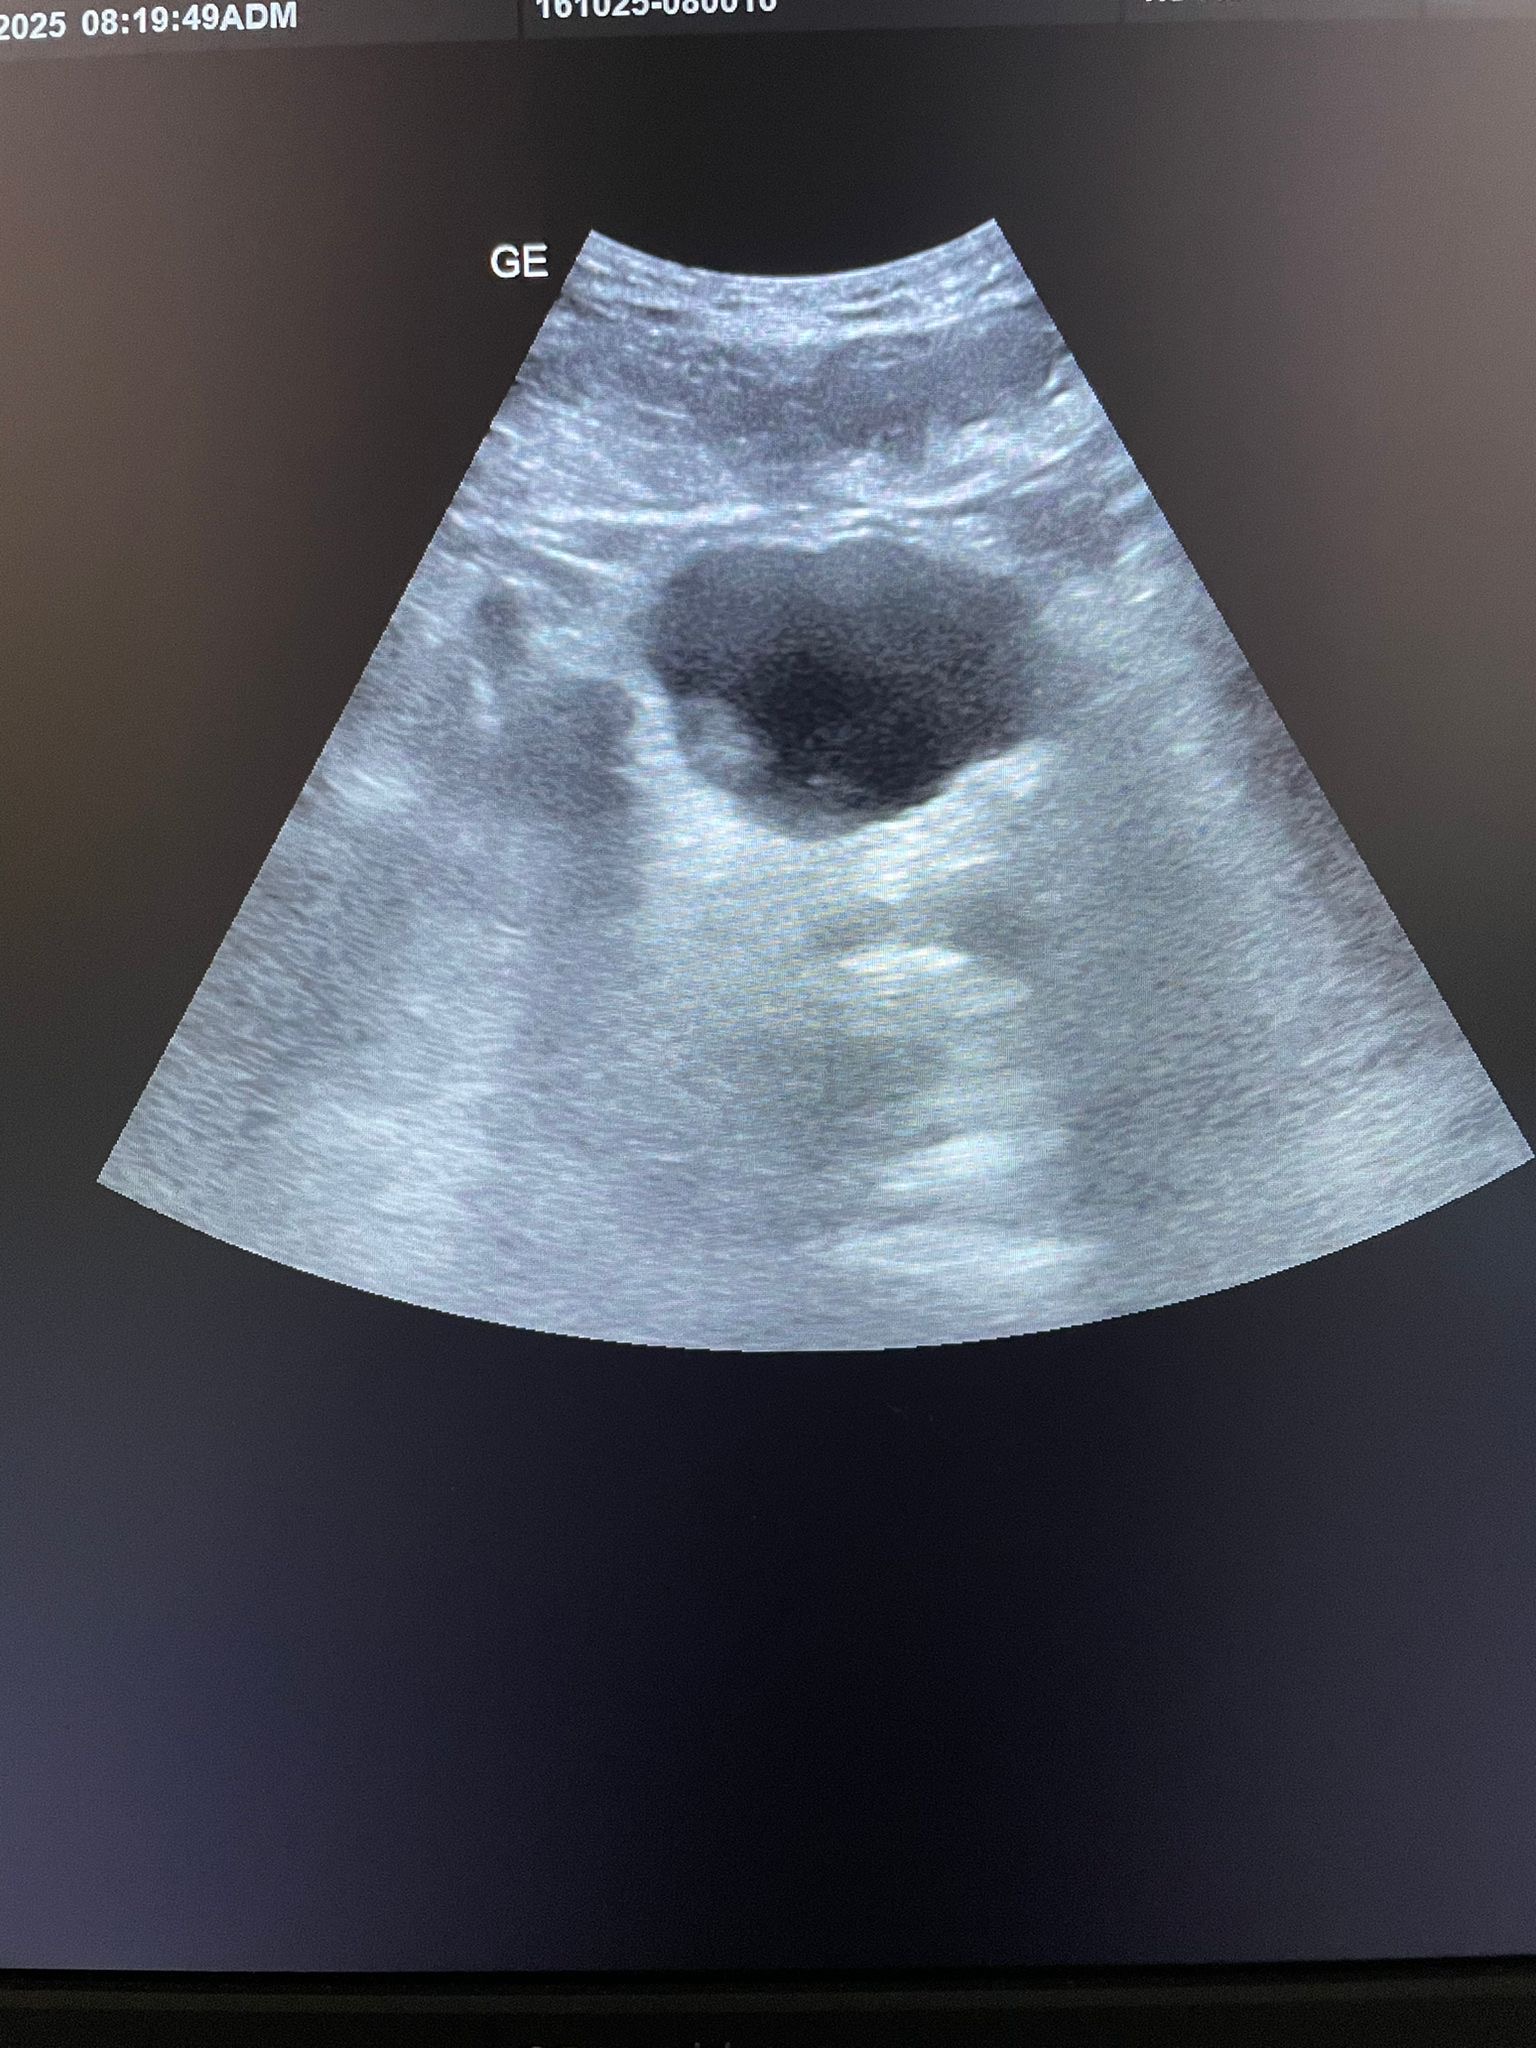

Hallazgos ecográficos

Se realiza ecografía abdominal donde se observa vejiga de adecuada repleción con imagen polipoide de 21x13 mm a nivel del piso vesical, discretamente a la derecha con signos de vascularización al examen doppler color. Se realiza URO-TC de abdomen y pelvis cuya conclusión es: microlitiasis renales bilaterales de 3-3,5 mm no obstructivas. Uréteres sin dilatación. Lesión intraluminal vesical de 15 mm en pared lateral derecha, cercana a la unión ureterovesical, con engrosamiento urotelial adyacente, de alta sospecha de neoplasia urotelial; menos probable coágulo organizado o pólipo inflamatorio dada la morfología y la ausencia de densidad cálcica. Sin adenopatías ilíacas o inguinales significativas.